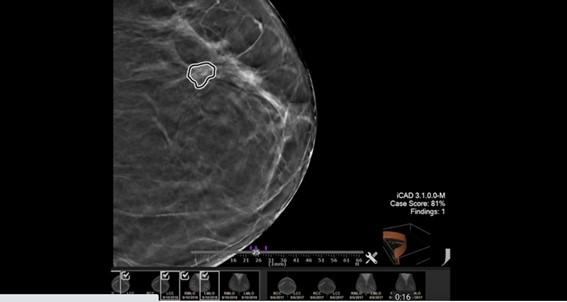

O Netherlands Cancer Institute (NKI) em Amsterdã, na Holanda, está desenvolvendo um novo projeto de diagnóstico de câncer com a utilização do modelo de software Nvidia AI Enterprise, para realizar varreduras em 3D com mais precisão. Disponível no LaunchPad, o pacote torna possível executar cargas avançadas de trabalho de inteligência artificial em servidores convencionais acelerados com VMware vSphere, entre os quais sistemas das marcas Dell, Hewlett Packard Enterprise e Lenovo.

Os pesquisadores do NKI, um dos centros de tratamento de câncer mais bem avaliados do mundo, treinaram previamente o modelo de IA em imagens de baixa resolução. Com a capacidade de memória oferecida pelo AI Enterprise, passaram a usar imagens de alta resolução que ajudam os médicos a reduzir falsos positivos e a definir melhor o tamanho e a localização de um tumor, para orientar o tratamento.

O software da Nvidia rodou no HPE Synergy, um sistema composto da HP Enterprise, para construir modelos de deep learning combinando fontes de dados 2D, 3D e IA para apontar a localização dos tumores antes de cada sessão de tratamento de radioterapia. “Os médicos podem usar essa solução como uma alternativa às tomografias computadorizadas e otimizar o plano de tratamento e validar o plano de radioterapia”, explicou Jonas Teuwen, líder do grupo que atua no instituto holandês.

Com o AI Enterprise, a equipe executou suas cargas de trabalho em GPUs Nvidia A100 de 80 GB em um servidor hospedado no Vale do Silício. A rede neural convolucional foi construída em menos de três meses e o treinamento utilizou cerca de 300 tomografias computadorizadas de pulmão, que foram reconstruídas e generalizadas para dados de cabeça e pescoço. Segundo a Nvidia, no futuro os pesquisadores do NKI esperam aplicar esses recursos também em radiologia intervencionista, para reparar artérias em cirurgias cardíacas e em outras intervenções.